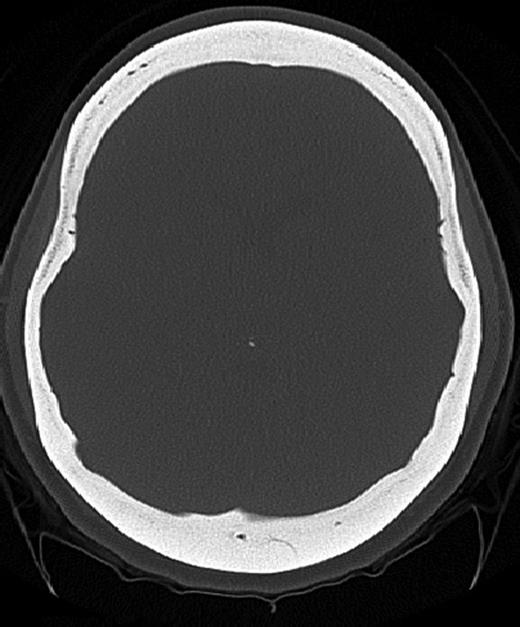

A 25-year-old female patient presented with 1-year history of occipital headache. The headache was increasing with coughing, sneezing and bending over. She had also complaints of intermittent bilateral hand numbness and bilateral feet burning. She was evaluated with magnetic resonance imaging (MRI), which showed Chiari I malformation with a 7 mm descent of cerebellar tonsils (Fig. 1 a and b). Computed tomography demonstrated diffuse calvarial thickening and loss of the medullary space (Fig. 2). Her past medical history was consistent with left eye surgery due to amblyopia when she was a child and she was blind in her left eye. Radioactive 131I treatment had been given due to the Graves’ disease and hyperthyroidism; therefore, she was hypothyroidic and was using levothyroxine daily. Her mother also was operated on because of the Chiari malformation. She had four siblings, and they did not have any pertinent medical history. Her physical examination revealed prominent occipital area and midfacial hypoplasia. Increased cortical thickness in her long bones was also demonstrated (Fig. 3 a–c). There were no abnormal findings on neurological examination except of left eye amorozis. The patient underwent surgery for decompression of posterior fossa. Large enough posterior fossa craniectomy with C1 laminectomy was performed with SSEP and MEP monitoring. Dura was opened in ‘Y’ shape, and duraplasty was performed with the pericranium. Arachnoid was kept intact. Her headaches improved significantly in postoperative period. She developed superficial wound infection, which was treated with simple washout and antibiotics.

Axial CT image (bone window) showing diffuse calvarial thickening and loss of the medullary space.